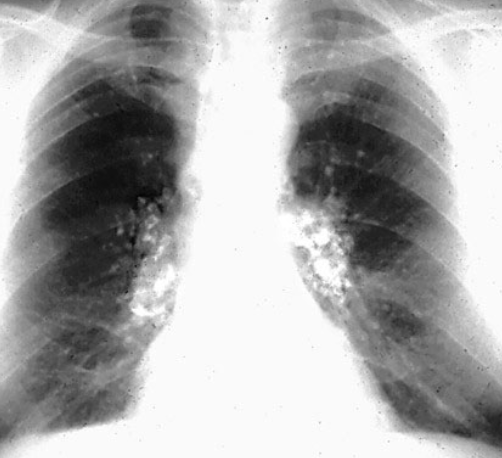

The skeleton is the most commonly involved organ system in Langerhans cell histiocytosis (LCH) and is by far the most common location for singlelesion LCH, often referred to as eosinophilic granuloma (EG) (the terms are used interchangeably in this article)For a general discussion of this disease please refer to the article on Langerhans cell histiocytosis (LCH). Ciao sono Sonia all'età di 5 anni mi sono stati diagnosticati 2 istiocitosi X, uno all'omero dx ed un altro al femore sx Ho fatto 2 anni di chemioterapia e fortunatamente sono guarita Oggi ho 29 anni faccio un lavoro dove il mio tempo lo passo all'impiedi e alzando pesi!. Download PDF Sorry, we are unable to provide the full text but you may find it at the following location(s) http//hdlhandlenet//15 (external link).

Additional terms may apply. Ciao sono Sonia all'età di 5 anni mi sono stati diagnosticati 2 istiocitosi X, uno all'omero dx ed un altro al femore sx Ho fatto 2 anni di chemioterapia e fortunatamente sono guarita Oggi ho 29 anni faccio un lavoro dove il mio tempo lo passo all'impiedi e alzando pesi!. Morphogenesis of some dense laminated bodies in histiocytosis X Article Sep 1975;.